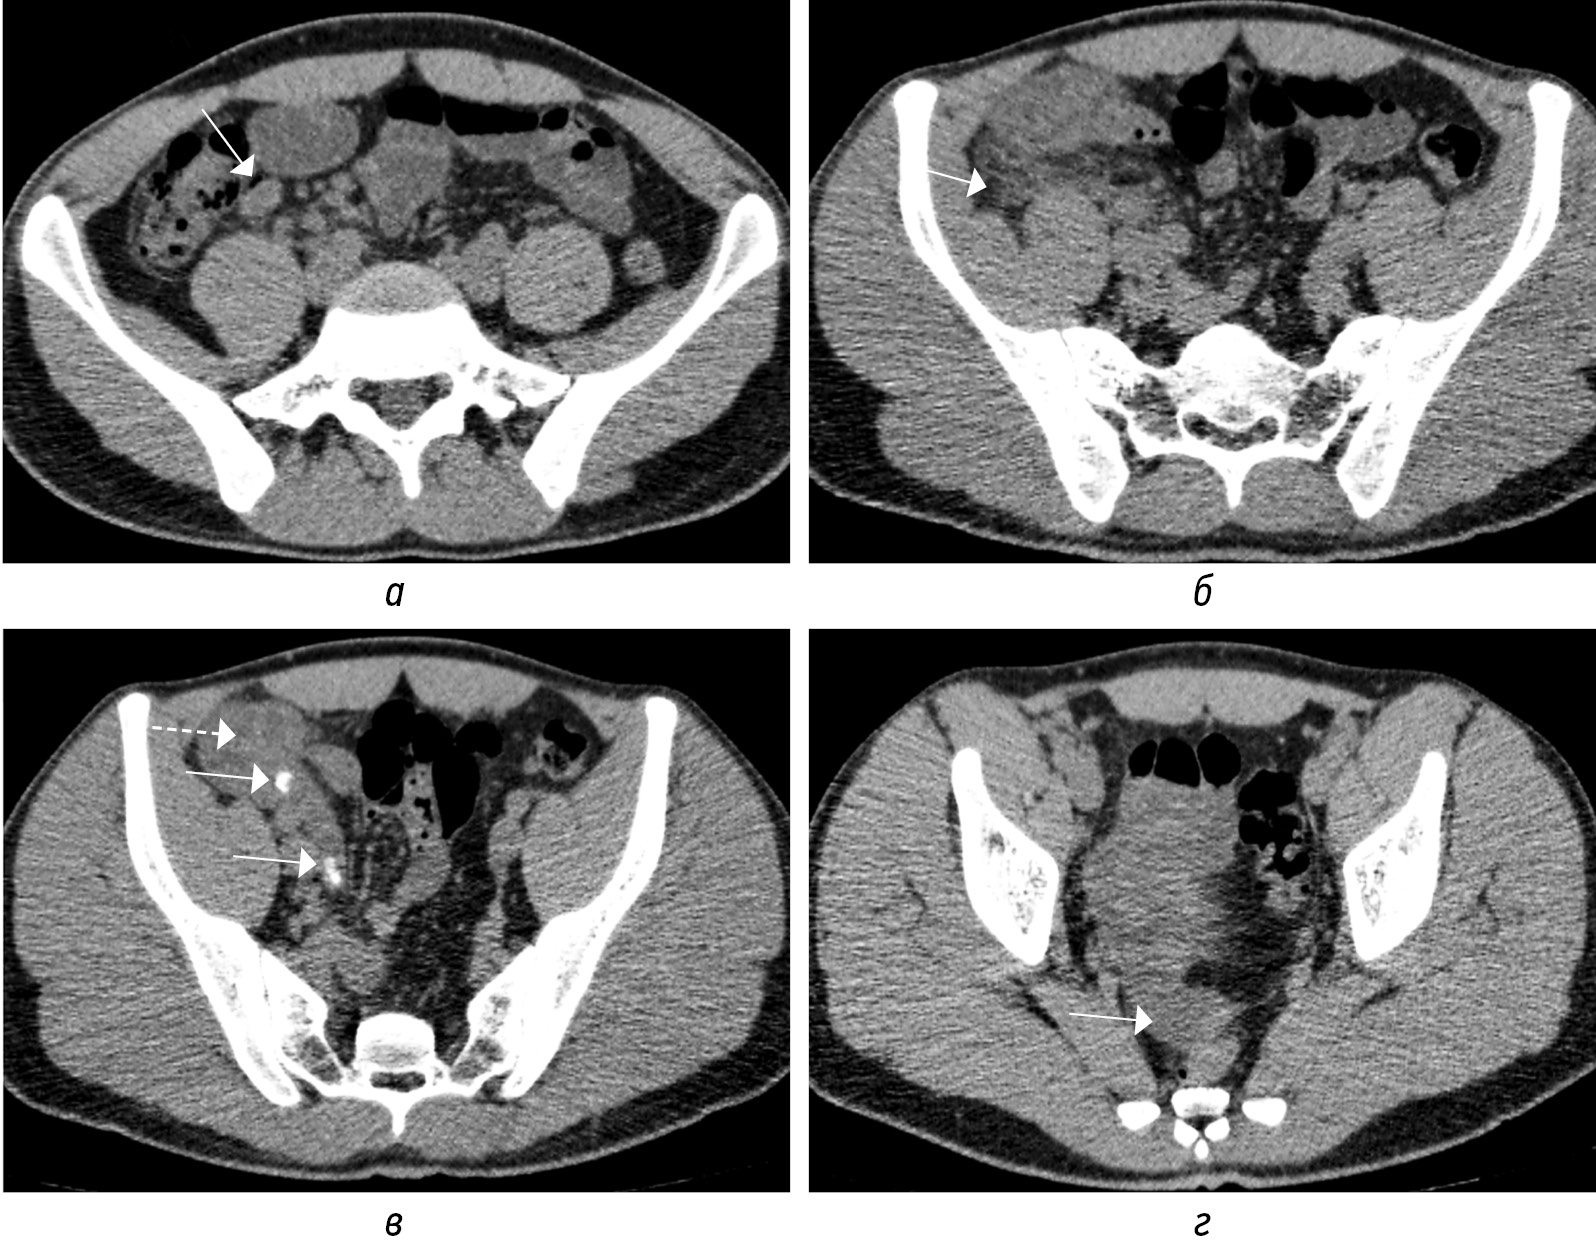

Просвет аппендикса может расширяться за счет неоднородного внутреннего содержимого без наличия (рис. 6, а, г) или с присутствием (рис. 6, б, в, д, е) аппендиколита. Другие косвенные признаки ОА: отек периаппендикулярной жировой клетчатки (рис. 7, а, б; 8, а, б); утолщение за счет отека прилежащей стенки кишки (рис. 9, а–г); расширение просвета кишки за счет газа иди жидкости с ослабленной перистальтикой; периаппендикулярное жидкостное скопление или абсцесс (рис. 10, а, б); лимфоаденопатия (рис. 11, а); абдоминальный выпот (рис. 11, г) [3, 16, 18].

Рис. 11. Нативные КТ-томограммы в аксиальной плоскости. Острый аппендицит с реактивной регионарной лимфоаденопатией (а, стрелка), отеком прилежащей жировой клетчатки (б, стрелка), с наличием аппендиколитов (в, стрелки), утолщением стенок слепой кишки (в, пунктирная стрелка), малого абдоминального выпота (г, стрелка)

Fig. 11. Native CT-tomograms in the axial plane. Acute appendicitis with reactive regional lymphadenopathy (а, arrow), edema of the adjacent adipose tissue (б, arrow), with the presence of appendicolitis (в, arrow), thickening of the walls of the cecum (в, dotted arrow), small abdominal effusion (г, arrow)